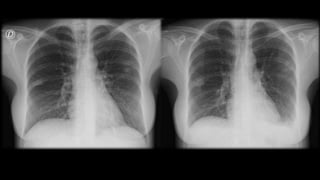

Una mujer de 31 años fue ingresada por faringoamigdalitis pultácea que no mejoró con tratamiento ambulatorio. Presentaba también molestias abdominales, náuseas, vómitos y diarrea. Las pruebas revelaron anemia grave, hipertransaminasemia e infiltrados pulmonares. El diagnóstico final fue bacteriemia por Fusobacterium necrophorum, trombosis de la vena yugular interna izquierda e infiltrados pulmonares, confirmando el síndrome de Lemierre.